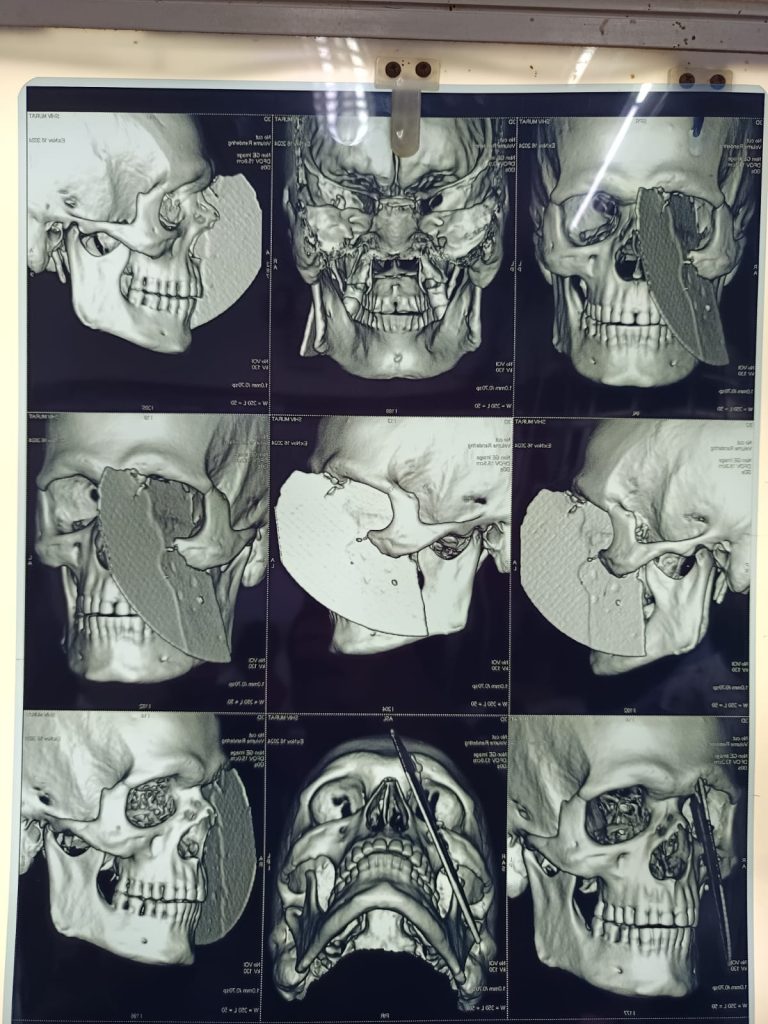

The razor-shape blade flew and hit the mason slicing open his face from top to bottom.

It penetrated his forehead, one eye, down the side of nose and also his chin.

Surgeons were then able to perform a four-hour operation to remove the blade.

Dr Sameer Mishra said: “The injury was complex due to the location of the metal shard.

“Which pierced both the nasal cavity and the eye socket.

“The procedure required careful coordination to prevent further damage and stabilise the patient.”